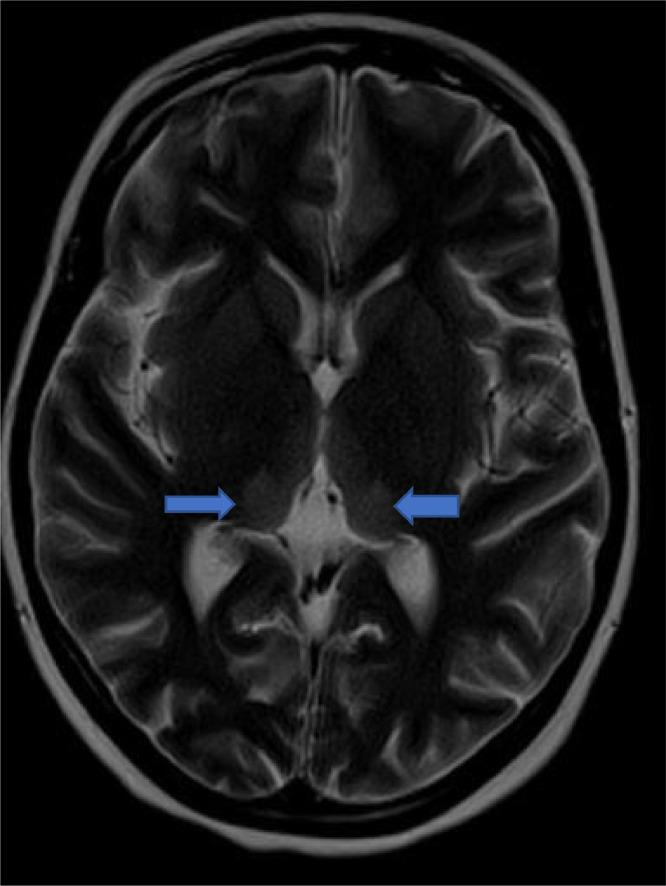

脑部磁共振成像:诊断孕妇盖耶-韦尼克脑病的一种安全且特异的工具:病例报告

Brain MRI: A safe and a specific tool in the diagnosis of Gayet Wernicke's encephalopathy in pregnant women: Case report.

Gayet-Wernicke encephalopathy (GWE) is a neuropsychiatric syndrome due to Vitamin B1 (thiamine) deficiency, fatal in 30% of cases and preventable if treatment is initiated early, characterized by the classic triad of encephalopathy, ocular involvement: ophthalmoplegia and/or nystagmus and ataxia. GWE is mainly observed in alcoholics, but can also appear in any state of malnutrition. In obstetrics, hyperemesis gravidarum can be complicated by GWE due to low thiamine stores and increased thiamine requirements. We report a case of Gayet-Wernicke encephalopathy complicating incoercible vomiting in a pregnant woman.

摘要

盖耶-韦尼克脑病(GWE)是一种由于维生素B1(硫胺素)缺乏引起的神经精神综合征,30%的病例会致死,若早期开始治疗则可预防,其特征为脑病、眼部受累(眼肌麻痹和/或眼球震颤)和共济失调这一经典三联征。GWE主要见于酗酒者,但也可出现在任何营养不良状态下。在产科,妊娠剧吐可因硫胺素储备不足和硫胺素需求增加而并发GWE。我们报告一例孕妇出现无法控制的呕吐并并发盖耶-韦尼克脑病的病例。